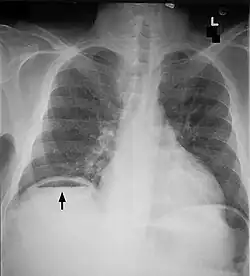

Medizin

In der Medizin bezeichnet eine Perforation den Durchbruch oder die Durchstoßung von Gewebe, welches eine Körperhöhle ummantelt.[7] Der Begriff wird dabei sehr vielfältig angewendet:

Krankheitsbedingte Perforationen kommen beispielsweise vor

- im Gastrointestinaltrakt: Speiseröhre, Magen, Zwölffingerdarm, Dünndarm, Dickdarm, Gallenwege

- im HNO-Bereich: Trommelfell, Nasenseptum

- in der Zahnmedizin

- in der Gynäkologie: Gebärmutter

- in der Urologie: Harnblase

- in der Augenheilkunde: Hornhaut

Eine Perforation der Speiseröhre ist immer lebensbedrohlich und kann durch einen Tumor ausgelöst werden. Geschwüre von Magen und Zwölffingerdarm können in die Bauchhöhle durchbrechen und ein akutes Abdomen auslösen. Auch Gallensteine können durch einen Druck auf die Gallenblasenwand eine Perforation bewirken. Eine Perforation des Dickdarms kommt zum Beispiel bei der Colitis ulcerosa vor. Im HNO-Bereich kann sich der Eiter einer Mittelohrentzündung durch eine Perforation des Trommelfells in den Gehörgang entleeren. Eine Perforation der Gebärmutter kann unter einer Spontangeburt nach einem Kaiserschnitt durch Ruptur der alten Narbe entstehen. Die Harnblase kann durch einen bösartigen Tumor perforiert werden, so dass sich der Urin in die Bauchhöhle entleert.